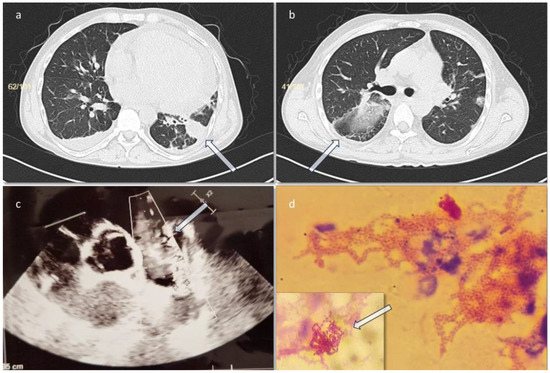

Introduction: Infective endocarditis (IE) is a disease that may frequently lead to significant morbidity and is associated with high mortality rates. Even though IE is classically caused by Gram-positive bacteria, Gram-negative bacteria may seldom ca...